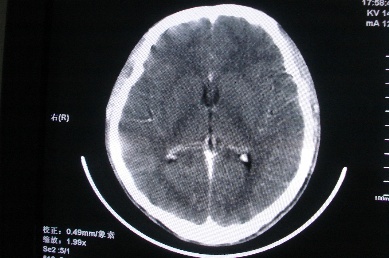

以下是引用zhangzhongshou在2007-4-18 17:49:00的发言:[br]脑实质内多发高密度结节影,支持肉芽肿得诊断,究竟是结核性、真菌性或寄生虫性的需结合临床,进一步检查确诊,但从影像上无法鉴别,只是临床上结核性肉芽肿最为多见而已。

以下是引用jiangjing在2007-4-18 16:57:00的发言:[br]考虑 感染性肉芽肿[结核可能性大],囊虫待排